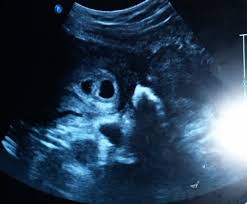

Some need them more often. Doctors use ultrasounds to check on your babies' health starting in the second trimester, most women with twins get ultrasounds every 3 to 4 weeks. By your 6th week of. Ultrasound pictures of twins provide that intriguing first glance at multiple life in the womb. At 6 week ultrasound, the embryo is barely 0.25 inches, which is the size of a sweet pea. Check out hundreds of amazing twin ultrasound images! We saw something else in the ultrasound that had a flicker in it but the doctor thought it may be blood flow. Anonymous asked in pregnancy & parenting.

Belly pictures, symptoms & ultrasound. Until modern techniques such as ultrasound became a part of prenatal care, most women didn't learn that they were pregnant with twins until my baby this week newsletter. Rafael ortega muñoz ginecologo especialista en ecografias 4d ciudad real. (in the united states, the chance of having twins is about 3 percenttrusted. Twin pregnancy (fraternal twins) ultrasound pregnancy resulted from implantation of 2 genetically different embryos. It really amazes me that this happens as much as it does. Doctors use ultrasounds to check on your babies' health starting in the second trimester, most women with twins get ultrasounds every 3 to 4 weeks. 6 week ultrasound identical twins. Reader noura i was kind enough to share ultrasound images of her di/di identical twins, whose ultrasounds look just like those of fraternal. The further along you are in your pregnancy the easier it becomes to see a separating. Being 6 weeks pregnant with twins seems like you're unlocking a new milestone of sorts. This ultrasound was taken when i was 8 weeks along. Ultrasound in the sixth week.